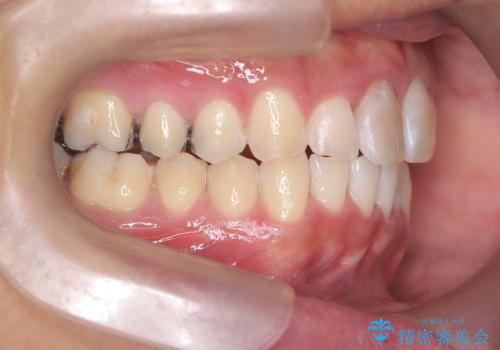

【インビザライン 非抜歯】歯の捻じれと歯のでこぼこを治したい!

- 「上の前歯の捻じれと下の前歯のでこぼこを治したい」を主訴に来院された患者様です。

矯正検査の結果、非抜歯で矯正可能だったためインビザラインで治療を行いました。

アーチの拡大とIPRで叢生を改善いました。

11ヵ月で矯正を終える事ができ患者様も大変ご満足されていました。